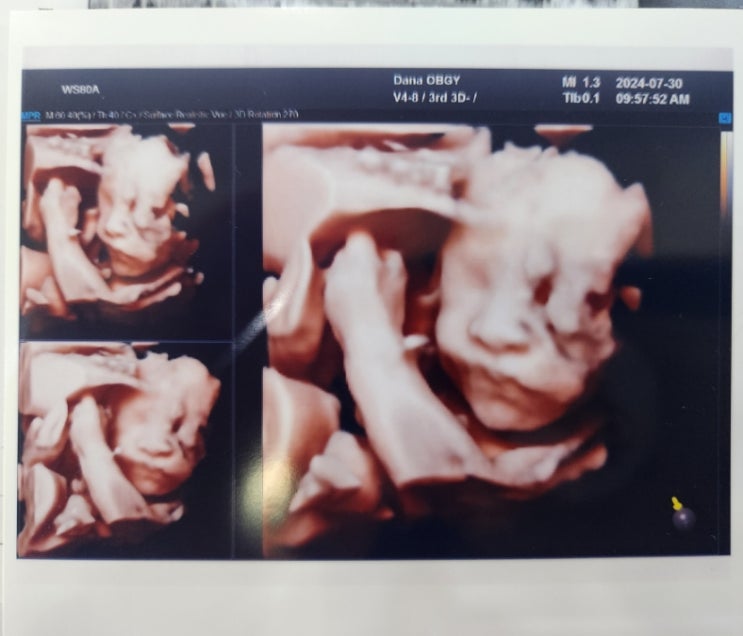

24주 6일 임당 검사, 입체 초음파

24년 7월 30일 화요일 9시 20분 진료 예약해서 9시 도착을 목표로 출발 용정 3차 우회 도로가 뚫려서 아침...